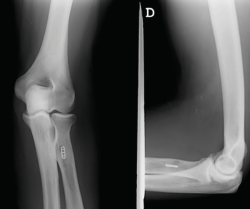

Se trata de un varón de 44 años con rotura del bíceps distal derecho de 6 meses de evolución, remitido para su valoración tras haber fracasado el tratamiento conservador que el paciente había decidido de forma voluntaria. A la exploración física, la movilidad del codo era completa pero manifestaba dolor en el vientre muscular a la contracción y un déficit de fuerza de flexión y pronosupinación que le impedía reincorporarse a su actividad laboral. Las pruebas diagnósticas preoperatorias como la resonancia magnética (RM) objetivaban la atrofia muscular, el ascenso y la casi ausencia completa de tendón bicipital (Figura 1).

Figura 1. Imagen de resonancia magnética preoperatoria. Se objetiva la atrofia muscular y la ausencia de cabo tendinoso.